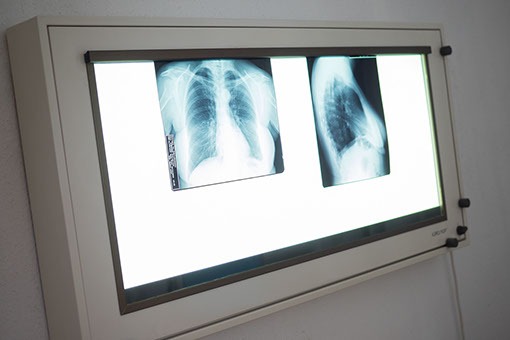

- Lungenröntgen

Falls Sie bereits ein Lungenröntgen durchgeführt haben, bringen Sie bitte den Befund und Bilder zur Untersuchung mit.